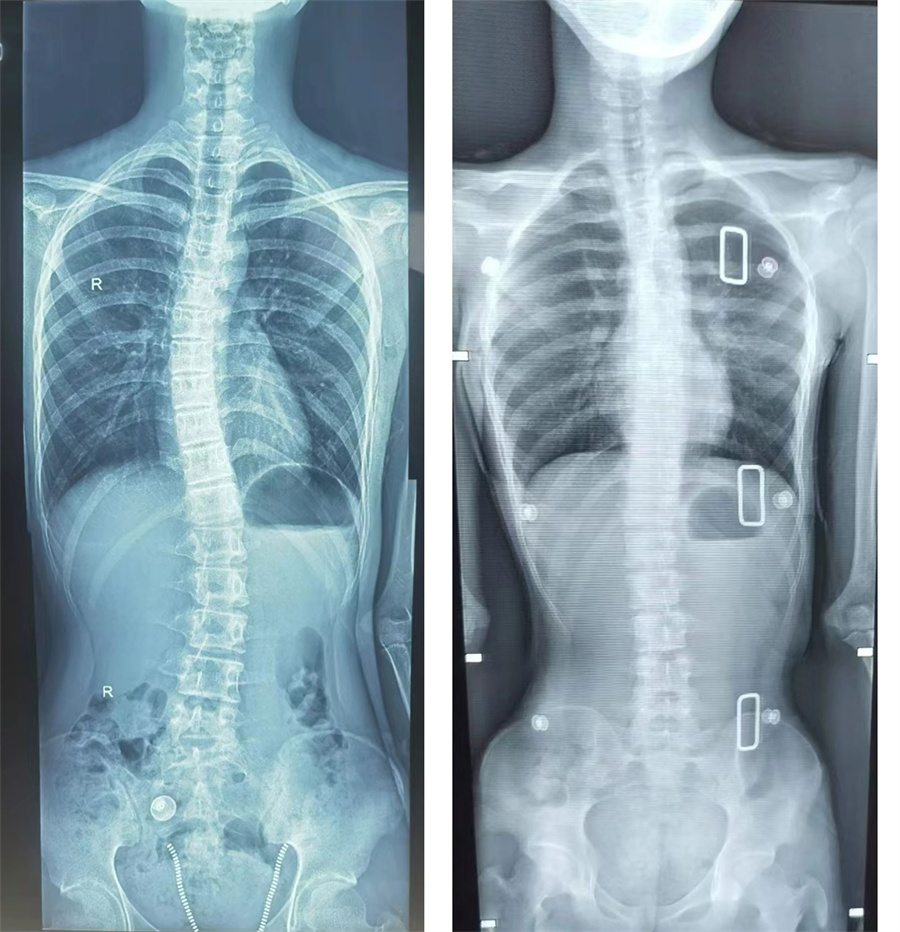

沉默的“青春病”,男孩脊柱竟长成C型

简单查体时,少年就暴露出明显的双肩不等高,弯腰做触地动作时,背部双侧不对称。X光片数据最终也证实了医生的判断:胸腰椎侧弯已达27度,相当于脊柱中段偏移了4.5厘米!“这就像正在生长的树苗突然被风吹歪了。”高凤奇主任用形象的比喻向家长解释,“好在发现及时,现在正是矫正黄金期。”

考虑到患儿骨骼尚未成熟,且侧弯角度处于20-40度的保守治疗窗口期,高凤奇主任决定对其采取支具保护的方式进行治疗。高凤奇主任介绍,孩子侧弯角度虽大于20度,但庆幸的是,脊柱不是先天性发育畸形,二是特发性的青少年脊柱侧弯。支具治疗就像给脊柱穿上隐形矫正衣,只要坚持规范佩戴一到二年,同时配合核心肌群训练,预计可将侧弯角度控制在安全范围内。